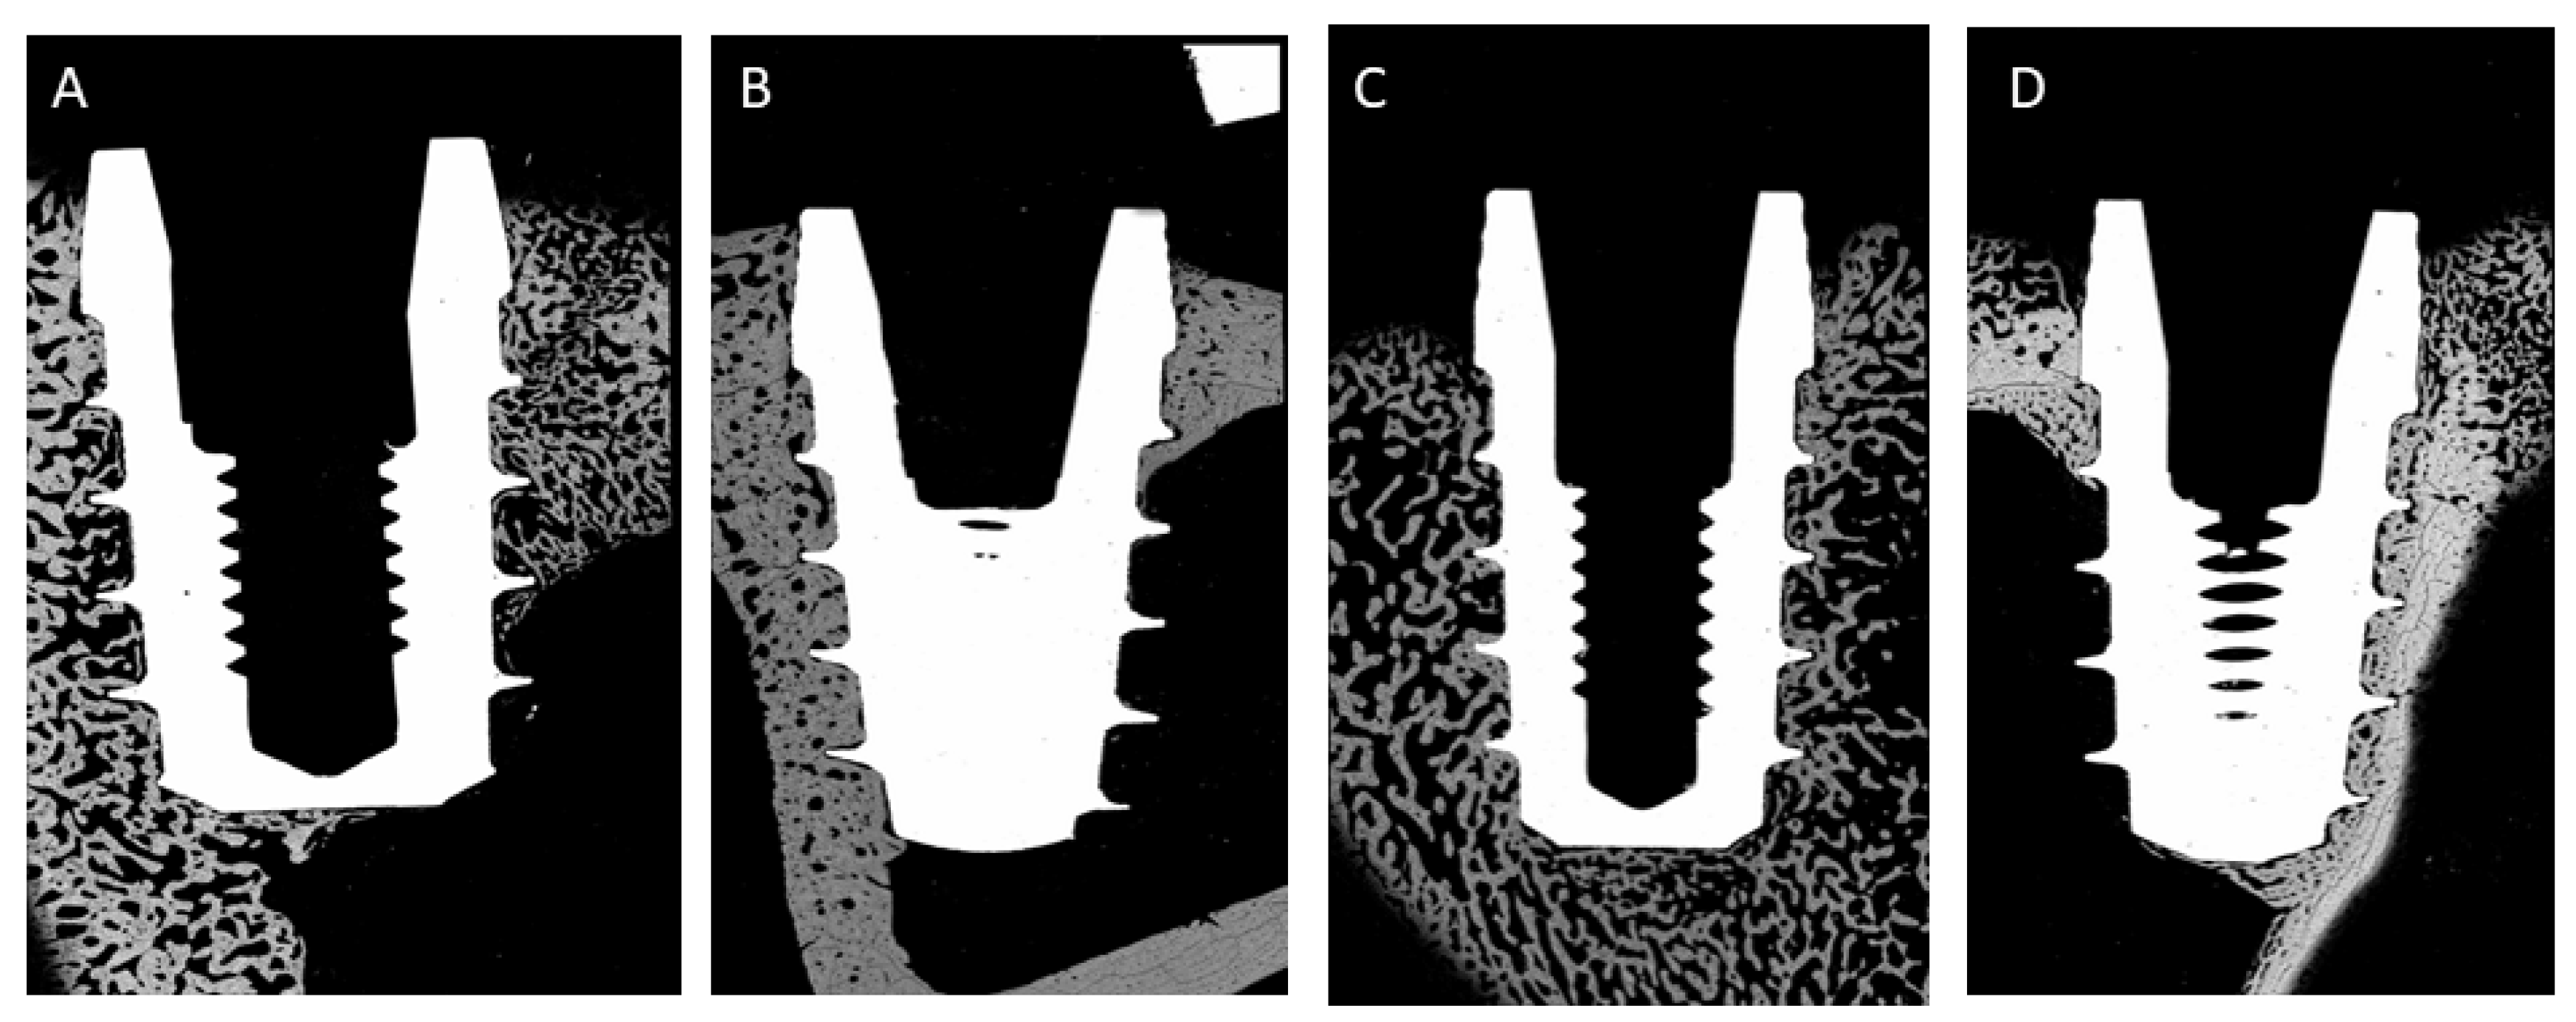

- Case A: 0.5 mm above the bone surface (h = +0.5).

- Case B: at the same level of the bone surface (h = 0).

- Case C: 0.5 mm below the bone surface (h = −0.5).

- t = 1.5 mm (cortical thickness).

- t = 2.5 mm (cortical thickness).